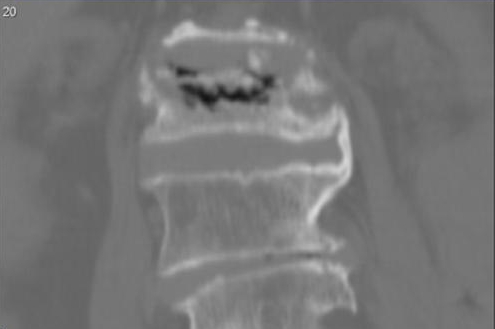

Наиболее эффективными методами диагностики являются рентгенография, компьютерная томография (КТ) и магнитно-резонансная томография (МРТ). Рентген позволяет увидеть изменения в тканях позвоночника. Снимки поврежденного позвонка делают с двух ракурсов.

При значительном прогрессировании заболевания на рентгеновских снимках можно заметить пирамидальные контуры пораженного позвонка. Компьютерная томография позволяет более детально рассмотреть его, выявляя очаги некроза и костные структуры под различными углами.

Магнитно-резонансная томография применяется для определения расположения жидкости в костных тканях и путей ее проникновения в поврежденный позвонок. Этот метод хорошо демонстрирует микротрещины и переломы на теле позвонка.